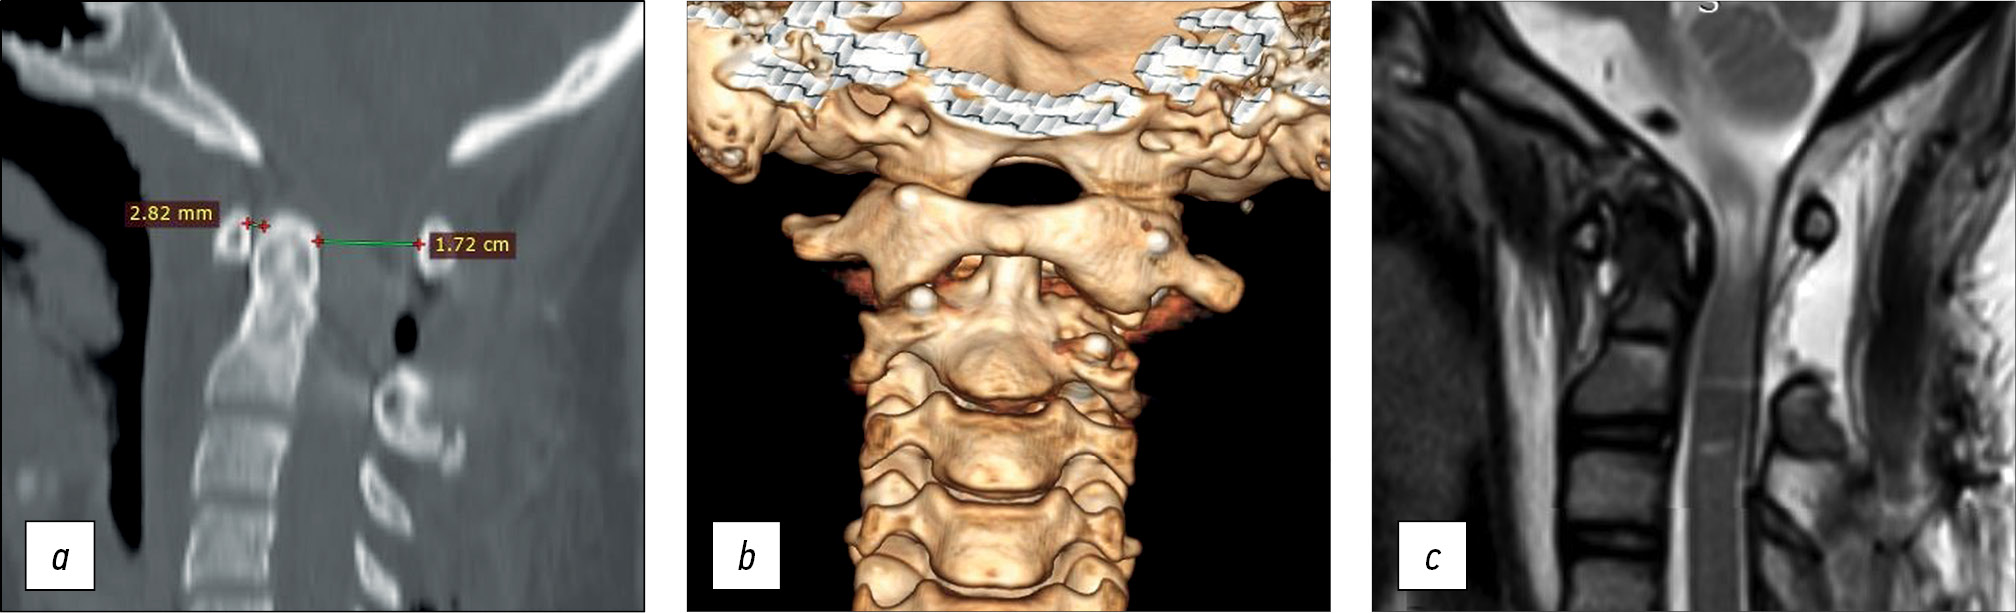

Given the gross atlantoaxial dislocation with spinal canal stenosis, spinal cord compression, and bone block formation in the left lateral atlantoaxial joint, correction of C1 subluxation under intraoperative halo-traction with the release of the left lateral atlantoaxial joint was decided. To improve the quality of preoperative planning and reduce the risks of a. vertebralis injury during the release of the lateral atlantoaxial joint, the patient underwent CT and myelo- and angiography of the cervical spine (Fig. 4). A customized 3D model of the craniovertebral region was made, showing the vertebral arteries and spinal cord based on CT myelography and CT angiography (Fig. 5).

Fig. 4. CT myelography and angiography: a — sagittal slice of CT myelography, b — 3D reconstruction of CT angiography. CT — computed tomography.

Fig. 5. 3D model of the patient’s cervical spine with visualization of the a. vertebralis and spinal cord: a — anterior view, b — lateral view, c — posterior view with the cervical vertebral arches removed.

The subluxation of the C1 vertebra was fully repaired with restoration of all craniovertebral ratios: the ADI and SAC were 2.82 mm and 1.72 cm, respectively. The spinal canal stenosis at the C1–C2 level was eliminated, and the fixation elements were appropriately implanted (Fig. 6).

Fig. 6. Рostoperative radiology examination: a — CT sagittal slice, b — 3D reconstruction of cervical CT, c — MRI sagittal slice with elimination of spinal canal stenosis and residual myelopathy. CT — computed tomography, MRI — magnetic resonance imaging.